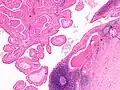

The appearance of this tumor under the microscope is unique. There are cystic spaces surrounded by two uniform rows of oncocytes, which are epithelial cells with abundant, granular, eosinophilic cytoplasm.[7] The cystic spaces have epithelium referred to as papillary infoldings that protrude into them. Additionally, the epithelium has lymphoid stroma with germinal center formation.

Low magnification micrograph of a Warthin tumor arising from the parotid gland. Low magnification micrograph of a Warthin tumor arising from the parotid gland.